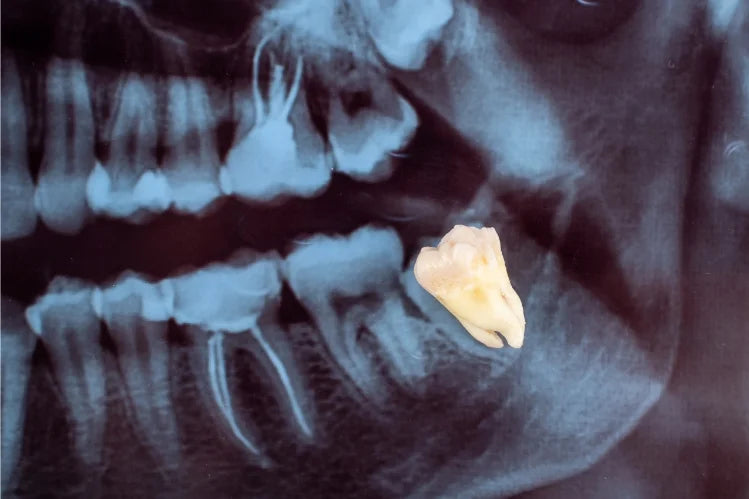

As shown in the image above, premolars are located between canines and molars. Adults usually have 8 premolars, 4 on the upper jaw and 4 on the lower jaw.

Molars are located at the back of your mouth, on the upper and lower jaws. Adults normally have 12 molars, including wisdom teeth. However, some adults have fewer molars due to extractions or missing wisdom teeth.